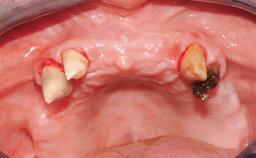

Rehabilitating an Edentulous Maxilla with a Fixed Dental Prosthesis Following Provisional Immediate Loading

This case features the flapless computer-guided placement of 7 bone-level implants, distributed to provide maximal support for the prosthetic framework. A rigid one-piece metallic framework was utilized as an interim restoration to reduce the risk of fracture associated with this prosthetic design. As part of the clinical examination, the SAC Assessment Tool was used, resulting in a surgical and restorative risk classification as “complex”.

Case Type Edentulous Maxilla

# of Implants 7